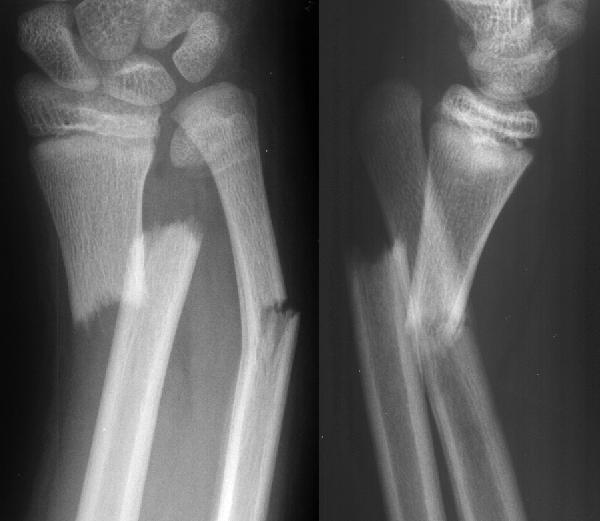

Диагностика

Закрытый перелом руки имеет много сходства с другими вариантами травмы, такими как сильных вывих, ушиб и другие. Именно поэтому, чтобы точно определить, что произошел перелом, врачи проводят нужную диагностику. Самым верным способом в данном случае будет проведение рентгенографии, которая позволит определить не только наличие перелома, но и его точную локализацию, позволяющую подобрать подходящее лечение.

Если рентгенография дает сомнительные и размазанные данные, врачи могут принять решение назначить дополнительное исследование с помощью компьютерной томографии. Она уже даст точную картину происходящему, определит не только наличие поврежденных костей, но еще и сосудов, мягких тканей и даже нервных окончаний. Только точные методы диагностики позволят определить наличие и характер травмы.